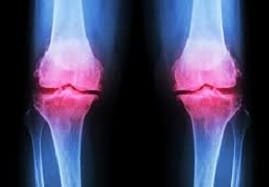

One of the most common causes of joint pain is arthritis. The two main forms of arthritis are osteoarthritis (OA) and rheumatoid arthritis (RA).

OA is most common in adults over age 40. It progresses slowly and tends to affect commonly used joints like the:

Joint pain due to OA results from a breakdown of the cartilage that serves as a cushion and shock absorber for the joints.

The second form of arthritis is RA. It more commonly affects women than men.

It can deform and debilitate the joints over time. RA causes pain, inflammation, and fluid buildup in the joints as the body’s immune system attacks the membrane that lines the joints.

A joint X-ray may be necessary to identify arthritis-related joint damage to access the gravity of the pain.